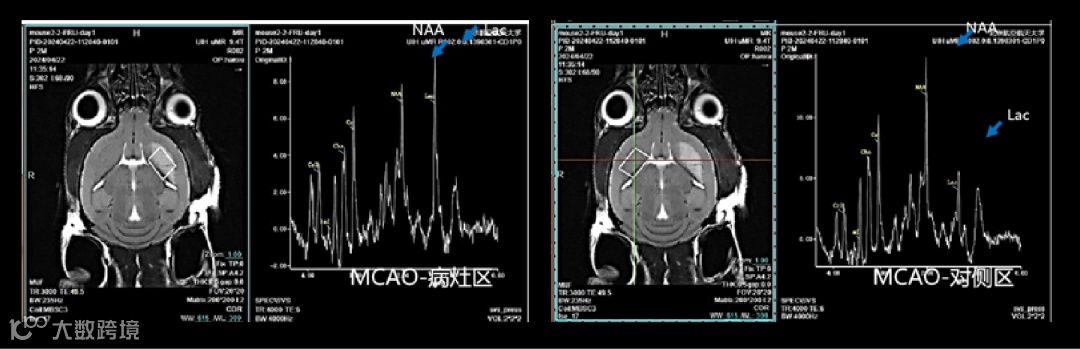

脑部磁共振波谱应用:

磁共振波谱成像,通过波谱图及数据,助力研究脑部代谢。例如脑卒中小鼠使用磁共振波谱成像,比较病灶区代谢物含量的变化(如图5),全方位为小动物脑科学研究提供影像支撑。

图5 小鼠脑部磁共振波谱成像